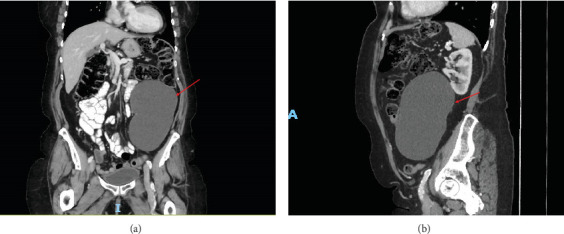

Urologists are commonly referred patients with retroperitoneal lesions and masses arising from or involving the kidney. In this case, the patient had a retroperitoneal mass identified on imaging which was initially concerning for a cystic renal neoplasm, but it was clearly distinct from all surrounding structures. Pathology found the very uncommon and unexpected diagnosis of a mucinous cystic neoplasm (MCN) with ovarian-type stroma suspected to have arisen from the pancreas. MCNs are lesions that most commonly arise in the ovaries, but less often can arise in extraovarian tissues. Of these extraovarian MCNs, primary retroperitoneal MCNs are exceedingly rare masses with some similarity to their pancreatic and ovarian counterparts. We present a case of an MCN found in the retroperitoneum and initially mistaken for a cystic renal mass, with histological markers and a concomitant pancreatic cyst that suggests possible pancreatic origin. Interestingly, no literature has described pancreatic MCNs without invasive features that have been found in the retroperitoneum without any formal tissue connection to the pancreas. The pathogenesis of retroperitoneal MCNs is still unknown, and as a result, the optimal treatment strategy is unclear.